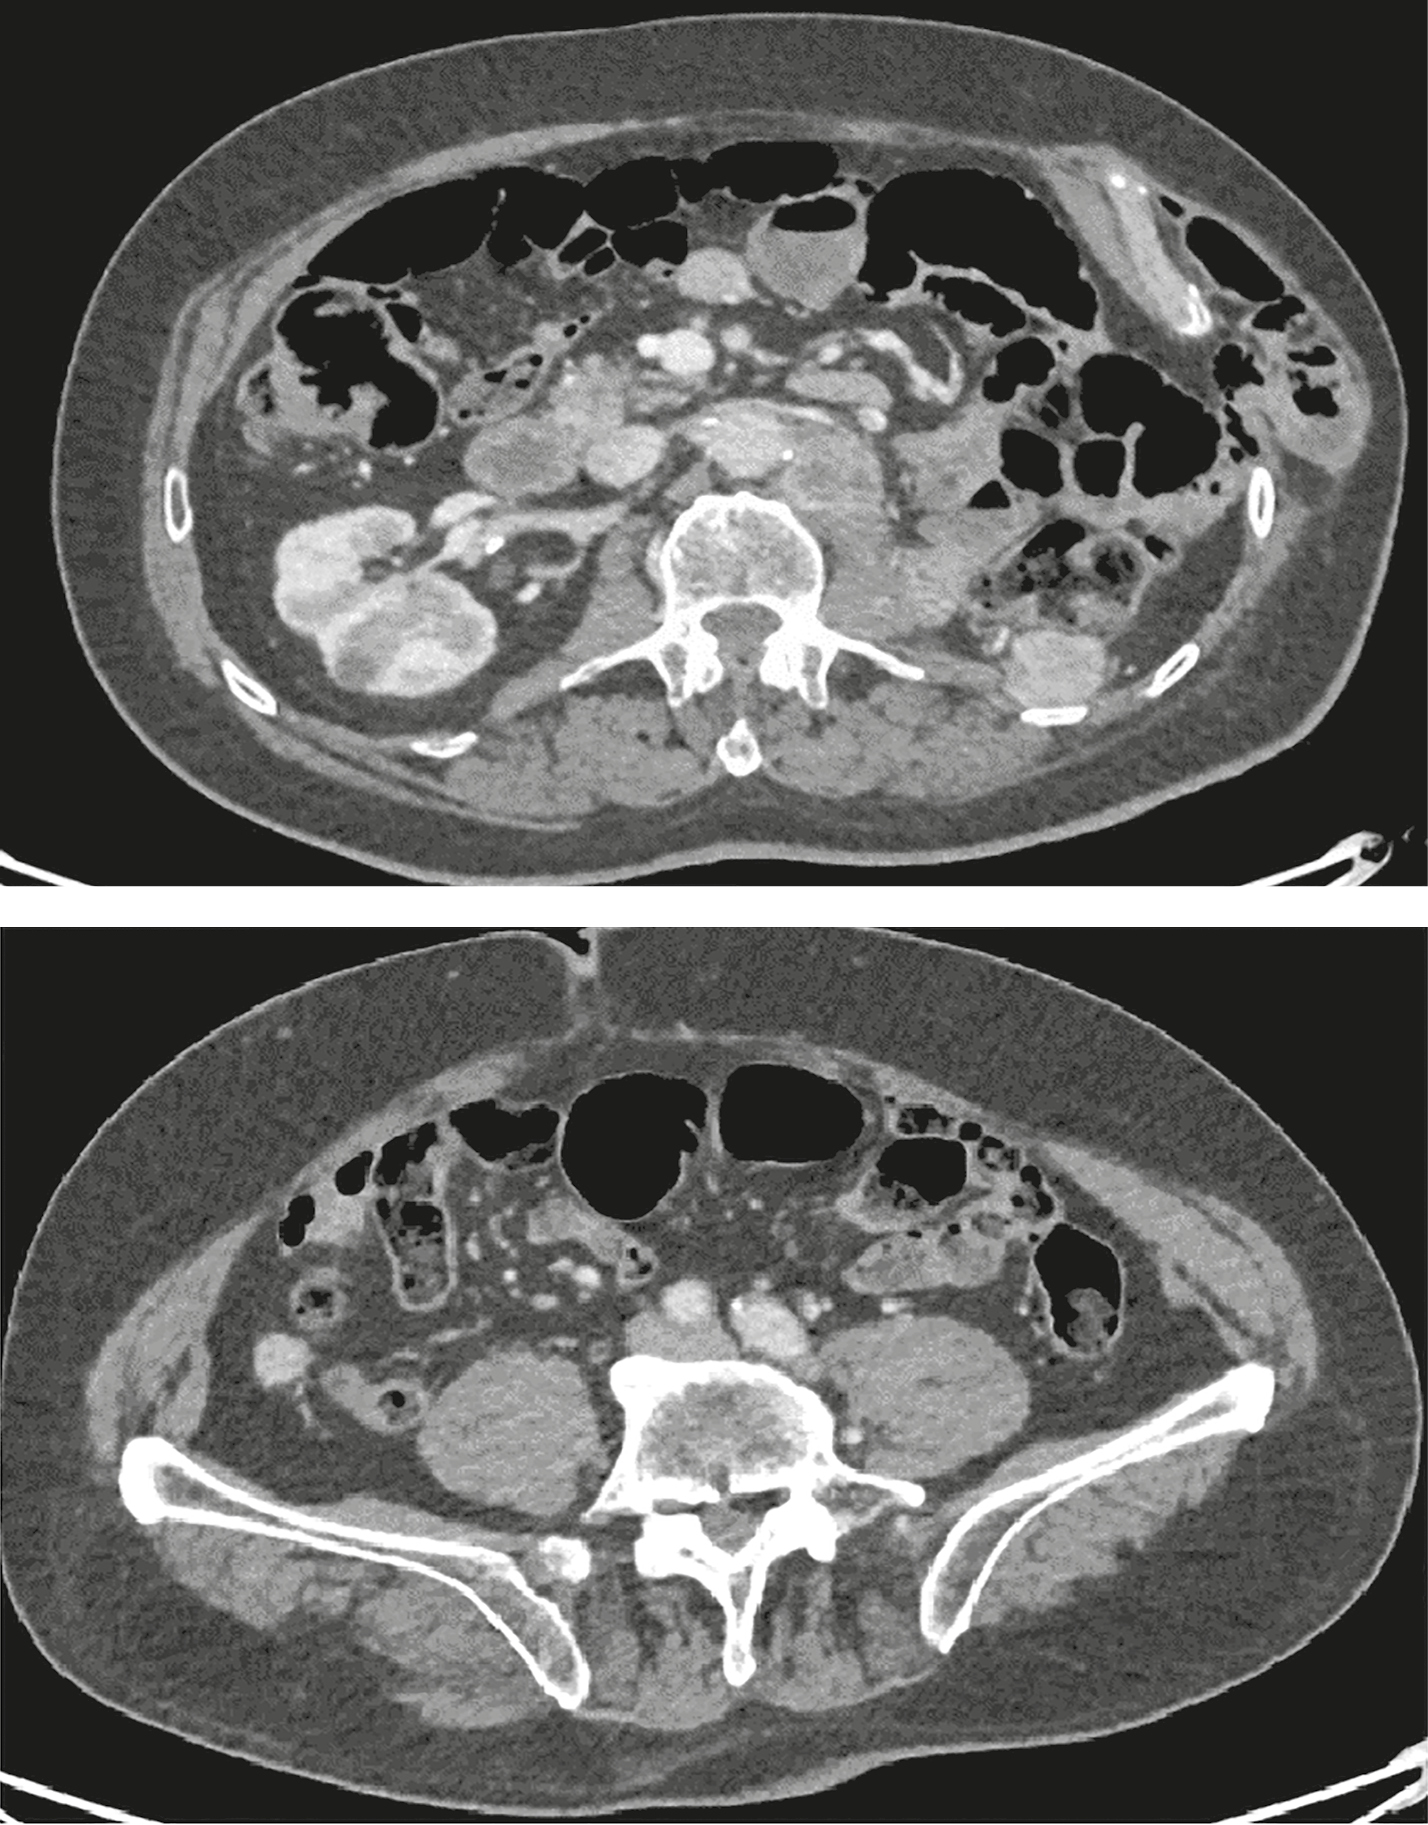

2. Рисунок 2. МСКТ органов брюшной полости пациента, июнь 2022 г. (стрелками обозначено гиперваскулярное объемное образование забрюшинно слева на уровне L1). | |